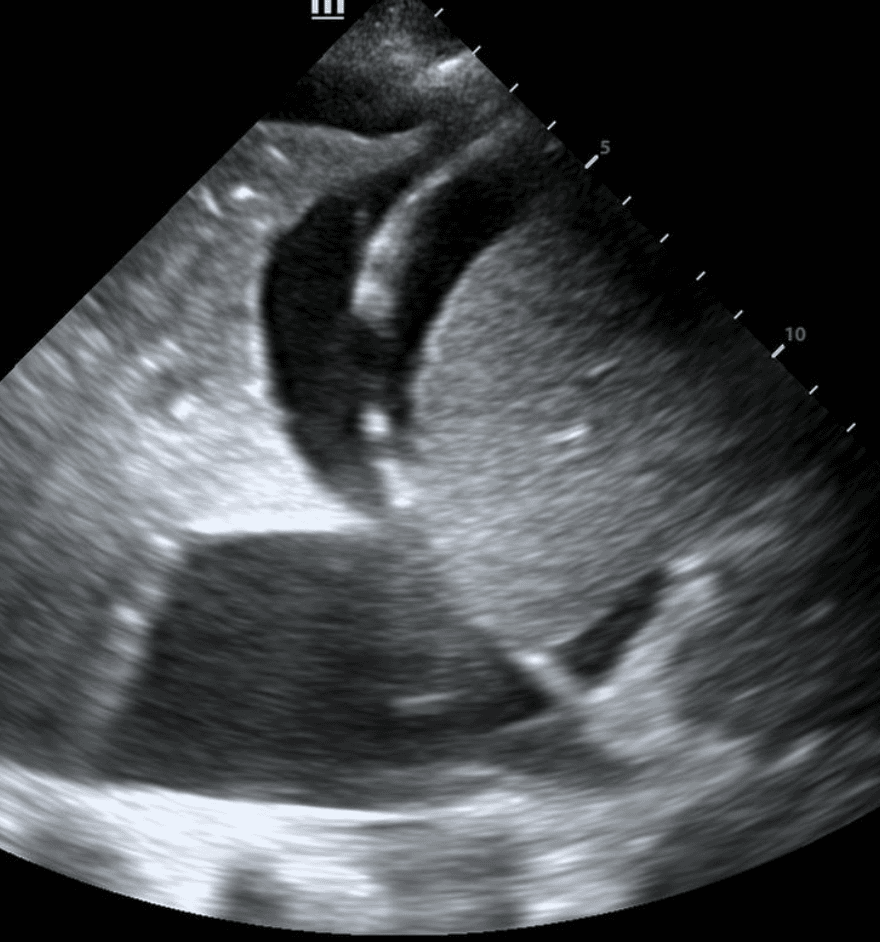

Next, identify the patient’s liver (if your probe is on the right side) or spleen (if your probe is on the left side). Above that, you will see a thin, hyperechoic line which is the patient’s diaphragm.

Finally, above the diaphragm, you will see one one of two things: if there are normal lungs without a pleural effusion, you will see an aerated lung obscuring the diaphragm during inspiration. This is referred to as a “curtain sign.”

If a pleural effusion is present, there will be an anechoic (ie. black) space above the diaphragm. Please note that an anechoic space below the diaphragm represents ascites; not a pleural effusion. Two other other features will stand out to you. Firstly, you will see a “spine sign.” Normally, the spine cannot be visualized above the diaphragm since aerated lung scatters ultrasound beams before it can reach the spine. However, a pleural effusion will allow sound waves to be transmitted to the spine and you will see the spine clearly visible above the diaphragm.